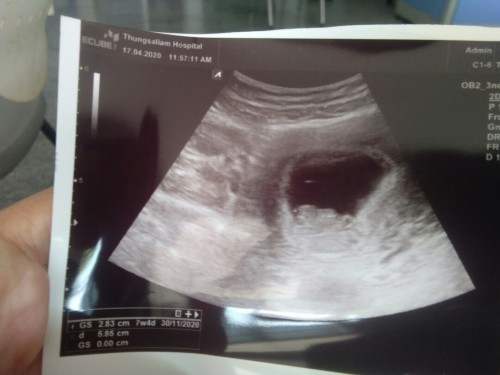

แม่! 🤰💖อวดรูปอัลตร้าซาวด์กัน

โชว์รูปแรกของเบบี้กันหน่อยน้า เพศหญิง👧หรือชาย🧑เอ่ยยย 😍🥰💜 17/09/2563

ผู้ชายค่ะ 21w แล้วค่ะตอนนี

ผู้ชายคะ ซาวด์ตอน17+5วีคคะ

ผู้ชายคัฟ ซาว์เมื้อวาน30w

ชายคร้า..ตอนนี้33+5คราฟ

ชายคะ ตอนนี้ 31+3 วีคแล้วคะ

ชายค่ะ ซาวด์ตอน 23 วีค